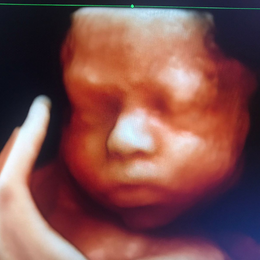

Ecografía del corazón fetal en 4D

- Las formas nuevas de ecografía pueden proporcionar imágenes en 5-D.

- 1 foto color ampliada en papel fotográfico color tamaño A4.